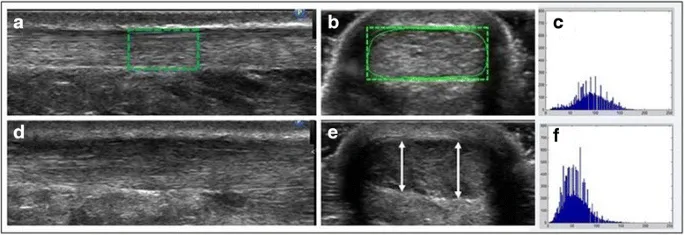

- Anisotropy: Crucial property; tendon/ligament echogenicity changes with insonation angle. Perpendicular beam = hyperechoic; oblique beam = hypoechoic (can mimic a tear).

⭐ Anisotropy is a critical artifact in MSK ultrasound; a normal fibrillar tendon can appear hypoechoic and mimic a tear if the ultrasound beam is not perpendicular to the tendon fibers.

- Tendinopathy: Hypoechoic, thick, neovascularization (Power Doppler).

- Anisotropy artifact: tendons appear falsely hypoechoic if not perpendicular to the ultrasound beam.